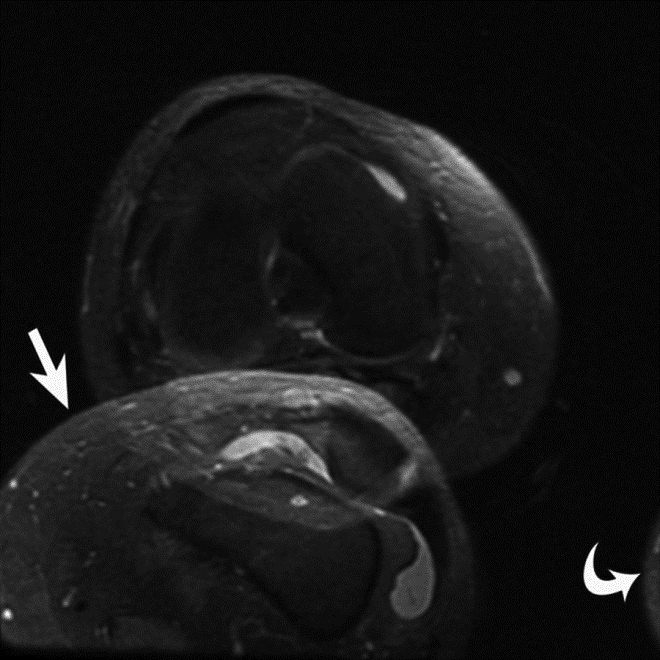

Wraparound Artifact. Axial proton-density-weighted MR image of the right knee demonstrates wraparound artifact (arrow) of the left knee, which is partially imaged (arrowhead).